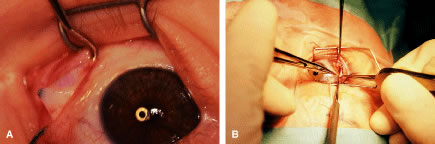

RECESSION PROCEDURE: FORNIX INCISION

This procedure is recession of the right medial rectus muscle. The eyelids are separated with a Barraquer open-blade wire eyelid speculum (Fig. 8). The open-blade design provides more room for exposure and makes it easier to pass the suture needles, especially in small children or when large recessions are performed. The globe is grasped with a Lester forceps at the limbus. It is best to grasp the limbus with the forceps held perpendicular to the globe and then to position the forceps so that they are rotated and lie tangential to the globe. Forced ductions are performed to detect any restriction of movement of the globe (Fig. 9).

|

The globe then is gently elevated from the orbit or proptosed at the same time it is abducted or adducted to prepare for the incision. Elevation of the globe helps to separate the horizontal rectus muscle from the inferior rectus muscle so that the inferior rectus muscle is not cut when the incisions are made. The conjunctiva is grasped by the assistant with a Manhattan toothed forceps (Fig. 10). This forceps has teeth that are angled outward and are designed to grasp conjunctiva, as well as the deeper subconjunctival tissue, so that when the blunt-tipped Westcott scissors cuts into the tented tissue, an incision is made into the conjunctiva and Tenon's capsule (Fig. 11A and B). If the incision does not completely penetrate Tenon's capsule and the intermuscular septum to the scleral surface of the eye, additional tissue (anterior Tenon's tissue and/or intermuscular septum) is grasped with the Manhattan forceps and at least one additional cut is made.